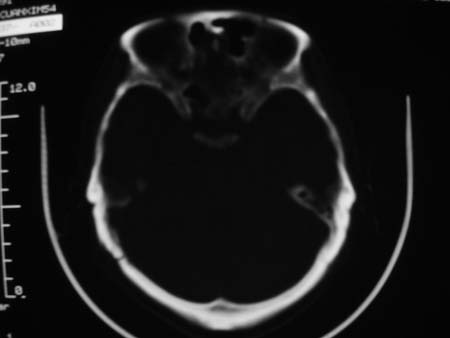

男,54岁,十天前被钢管打伤头顶部,现自述头部不适,视物模糊,并于两天前发觉右枕部有包块,既往未有明显异常.

颅骨多处骨质不完整,内板变薄,右侧额颞部局部呈“穿凿样”骨质缺损,相应区硬膜外密度略增高。多考虑:骨嗜酸性肉芽肿!

右枕骨及双额角均有类似改变,考虑骨髓瘤可能性大,建议查本周氏蛋白.

颅骨多处骨质不完整,内板变薄,右侧额颞部局部呈“穿凿样”骨质缺损,相应区硬膜外密度略增高。多考虑:骨髓瘤或骨嗜酸性肉芽肿!

颅骨多处骨质不完整,内板变薄,右侧额颞部局部呈“穿凿样”骨质缺损,缺损骨质边缘锐利无硬化,相应区硬膜外密度略增高。多考虑:骨嗜酸性肉芽肿!

颅骨多处骨质不完整,内板变薄,右侧额颞部局部呈“穿凿样”骨质缺损,相应区硬膜外密度略增高。多考虑:骨髓瘤或骨嗜酸性肉芽肿!10天前受伤,不会在2天前才发现头部包块,估计与外伤无关.

骨嗜酸性肉芽肿密度可以这么高么?能不能是脑膜瘤.